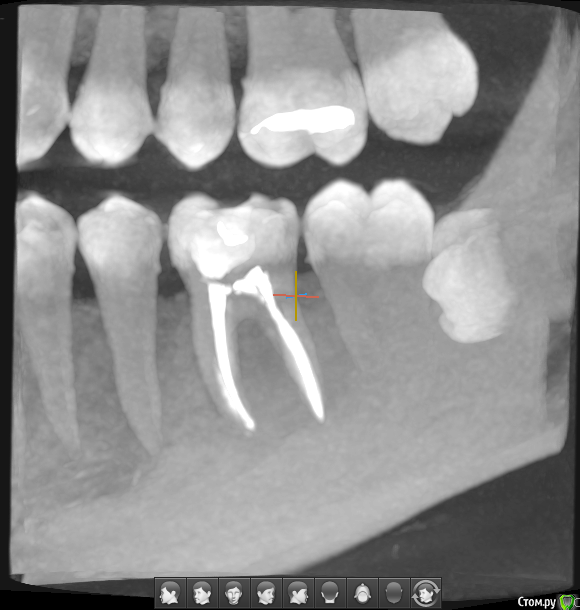

Лечили пульпит 30-го зуба, после пломбирования каналов (гуттаперчей, горячим методом) в течение пары недель (была установлена временная пломба) ощущалась боль при надавливании на зуб. Боль не прошла, пришлось распломбировать один из каналов, в котором предположительно была проблема (пластиковый "штифт", кажется).

После распломбировки одного канала ожидали полторы недели, боль осталась, на следующем приеме распломбировали все каналы, поставили временную пломбу. Перед приемом был сделан снимок 30-го зуба и двух ближайших зубов. Прошло еще пару дней, зуб все так же болит при надавливании. В чем (хотя бы ориентировочно) может быть проблема? На снимке (фото которого прилагаю) видно, что материал не выходит за верхушку корня. Трещин, кажется, тоже нет. Но в чем тогда проблема?( Если боль не пройдет, я, честно говоря, даже и не знаю, что делать...

Доброго. Речь скорее всего о 36 зубе. У Вас имеются зубные отложения (камни см.рис.) которые так же могут поддерживать воспалительный процесс влияющий на возникновение болей в зубе при надавливании. Также необходимо дифференцировать нет ли болевого синдрома из-за 38 зуба ( неправильное положение с упором в 37 ). Если даже все вышеперечисленное не является причиной болей , то может болеть зуб , иногда бывают ответвления в сторону от канала ближе к верхушке корня , которые пройти ( пролечить) крайне затруднительно , или не представляется возможным физически ....исключите сначала 2 первых пункта.